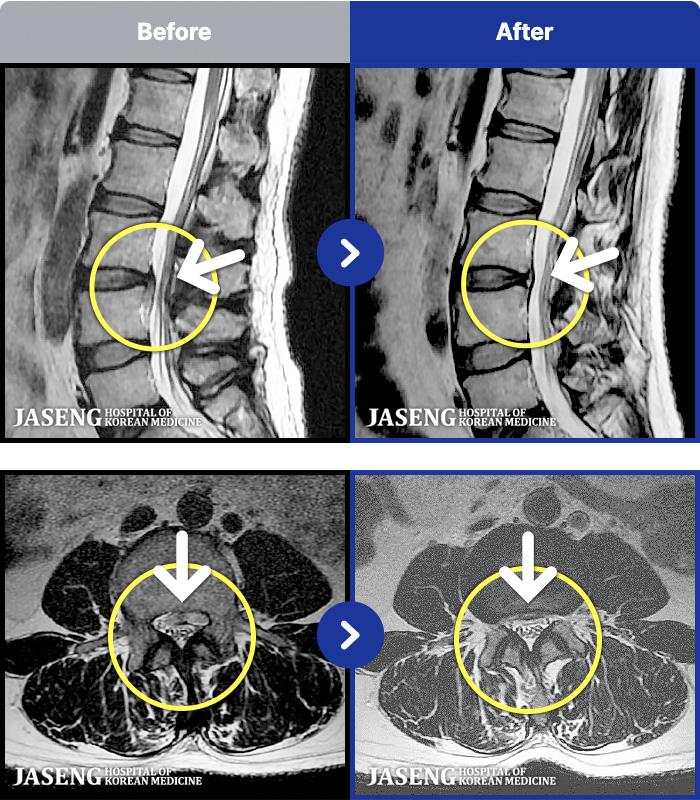

[뱸] 19.11.28~25.05.06